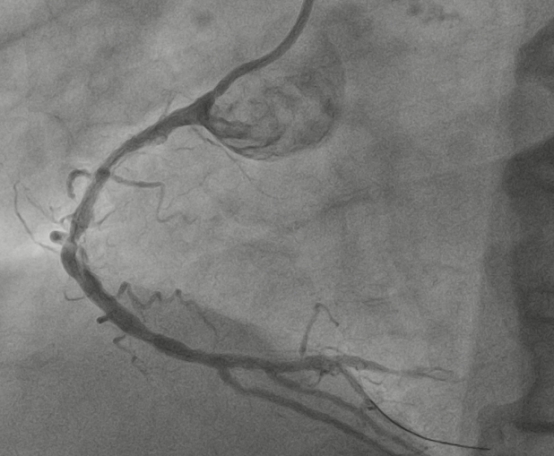

10月24日凌晨1时,67岁的姜大叔突发胸痛并持续加重,伴有大汗,在家忍受了4小时后才拨打了120电话送到我院,经绿色通道行急诊冠脉造影见:右冠急性闭塞、左主干重度狭窄、前降支中远段慢性闭塞、回旋支近段重度狭窄。一边血管堵塞一边血管开口接近闭塞,相当于心肌只有很少血液供应,随时有猝死风险。

图2:左主干开口及近段重度狭窄、前降支慢性闭塞